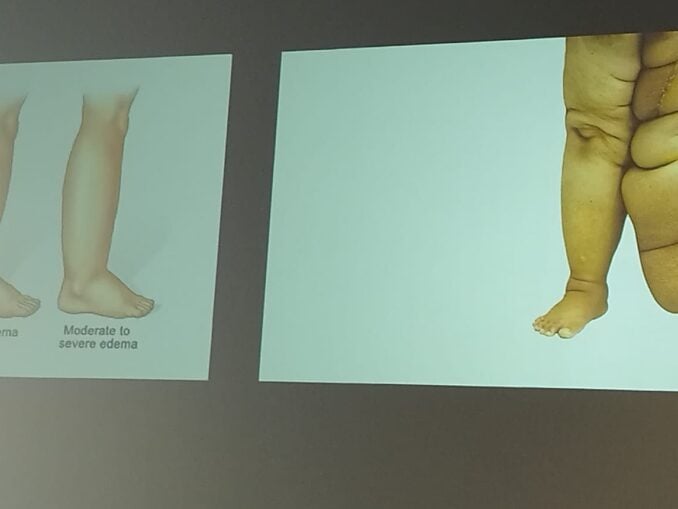

Pandemie de limfedem în lume. În jur de 250 de milioane de oameni din toată lumea suferă de limfedem. Elefantiazisul e stadiul grav. Ce spune un renumit medic de la Viena.